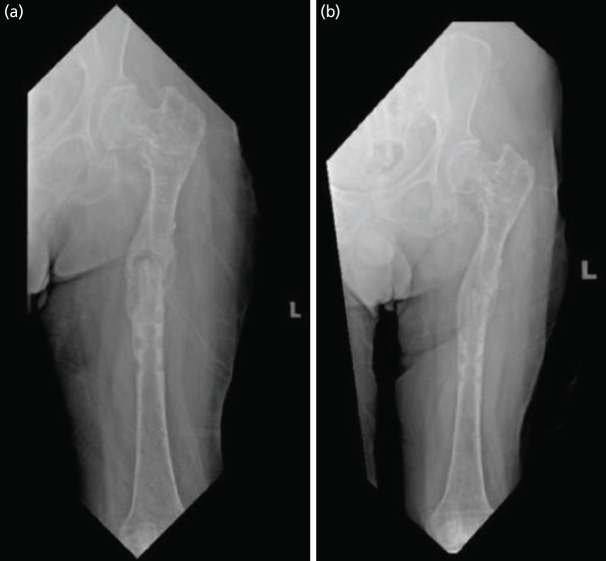

骨不连是指骨折修复过程中出现的断裂,可通过连续的临床和影像学评估来识别。脓毒性骨不连和无菌性骨不连的区别是必要的,因为治疗策略是根本不同的。骨不连最常用手术治疗,因为它有助于提供机械稳定性和良好的生物环境来促进骨愈合。然而,也有保守治疗的选择,即使用功能支架进行适当的固定,这是外科手术的另一种选择,在胫骨不连病例中被广泛报道。迄今为止,还没有功能性支架成功治疗股骨骨不连的病例报道。本病例报告详细介绍了使用功能性支架成功治疗一位因骨折相关感染导致股骨不愈合的智障男士。

Non-union refers to a disruption in the process of fracture repair, which can be identified through sequential clinical and radiographic assessments. The distinction between septic and aseptic non-union is essential because the treatment strategies are fundamentally different. Non-unions are most often treated surgically as it helps to provide both mechanical stability and good biological environment to promote bone healing. However, there is also the option of managing it conservatively by proper immobilisation using functional brace which is an alternative for surgical procedures and widely reported in tibia non-union cases. To date, there has been no reported case of femur non-union successfully treated with a functional brace. This case report details the success of treatment using a functional brace in a mentally disabled gentleman who sustained a femur non-union following a fracture related infection.